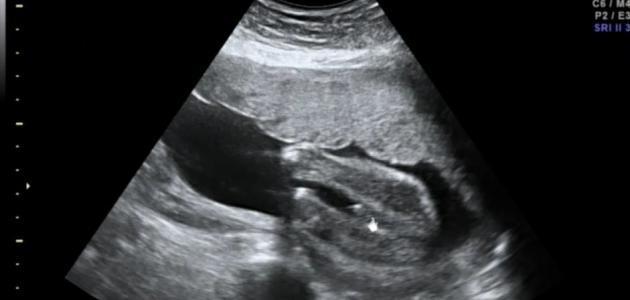

وزن الجنين في الشهر السابع

يعدّ الشهر السابع مميّزاً في حياة الجنين؛ وذلك لأنّه يتطوّر وينمو خلاله بشكل ملحوظ، ويبدأ وقت الشهر السابع تحديداً من الأسبوع السابع والعشرين إلى الأسبوع الثلاثين من فترة الحمل، وهناك زيادة في حجم الجنين وتطوّر ملحوظ خلال أسابيع هذا الشهر على النحو التالي:

- في الأسبوع الأول من الشّهر السّابع: يبلغ وزن الجنين في الأسبوع السّابع والعشرين ما بين 800 غرامٍ أو 890 غراماً، ويعود الأمر لطبيعة كلّ طفل، فإنّ الوزن المحدد هنا هو الوزن الطبيعيّ للطفل في مراحل الحمل، ولكن قد يختلف وزن الأطفال لاختلاف طبيعة غذاء وصحّة المرأة الحامل، ويصل طول الجنين في هذا الأسبوع إلى ستة وثلاثين سنتيمتراً ونصف تقريباً.

- في الأسبوع الثّاني من الشّهر السّابع: يبلغ وزن الجنين في الأسبوع الثّامن والعشرين كيلوغراماً واحداً تقريباً، وأمّا طوله فيزداد بمقدار سنتمترٍ واحد تقريباً أي يبلغ سبعة وثلاثين ونصف سنتمتر، وفي هذا الأسبوع يبقى الدّماغ في مرحلة النّموّ والتّطوّر، وتبدأ رموش العينين بالتكوّن ولكن لا يستطيع الجنين أن يمارس عمليّة الرمش.

- في الأسبوع الثّالث من الشّهر السّابع: يزداد وزن الجنين ما يقارب 200 غرام، ويبلغ وزنه كيلوغراماً واحداً و200 غرامٍ تقريباً وفي بعض الأحيان أقلّ بمعدّل 50 غراماً، وتأتي هذه الزّيادة الواضحة في وزن الجنين؛ نتيجةً لزيادة حجم الرأس وتطّور نموّ بعض أعضاء الجسم الأخرى وظهور الشّعر على الرّأس، كما يبلغ طول الجنين 38.5 سنتيمتر تقريباً.

- في الأسبوع الأخير من الشّهر السّابع: ينتهي نموّ الجنين في الأسبوع الثلاثين من الشّهر السّابع، وقد تحدث الولادة المبكّرة في هذا الشّهر أحياناً ويوضع الطّفل بعدها في الخداج للاهتمام بحالته الصحيّة.